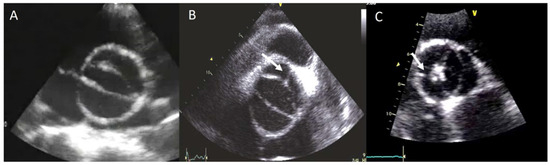

2. Diagnosis and BAV Phenotype

- Brandenburg, R.O.J.; Tajik, A.J.; Edwards, W.D.; Reeder, G.S.; Shub, C.; Seward, J.B. Accuracy of 2-dimensional echocardiographic diagnosis of congenitally bicuspid aortic valve: Echocardiographic-anatomic correlation in 115 patients. Am. J. Cardiol. 1983, 51, 1469–1473. [Google Scholar] [CrossRef]

- Sun, B.J.; Lee, S.; Jang, J.Y.; Kwon, O.; Bae, J.S.; Lee, J.H.; Kim, D.-H.; Jung, S.-H.; Song, J.-M.; Kang, D.-H.; et al. Performance of a Simplified Dichotomous Phenotypic Classification of Bicuspid Aortic Valve to Predict Type of Valvulopathy and Combined Aortopathy. J. Am. Soc. Echocardiogr. Off. Publ. Am. Soc. Echocardiogr. 2017, 30, 1152–1161. [Google Scholar] [CrossRef]

- Jilaihawi, H.; Chen, M.; Webb, J.; Himbert, D.; Ruiz, C.E.; Rodés-Cabau, J.; Pache, G.; Colombo, A.; Nickenig, G.; Lee, M.; et al. A Bicuspid Aortic Valve Imaging Classification for the TAVR Era. JACC Cardiovasc. Imaging 2016, 9, 1145–1158. [Google Scholar] [CrossRef] [PubMed]

- Sievers, H.-H.; Schmidtke, C. A classification system for the bicuspid aortic valve from 304 surgical specimens. J. Thorac. Cardiovasc. Surg. 2007, 133, 1226–1233. [Google Scholar] [CrossRef]